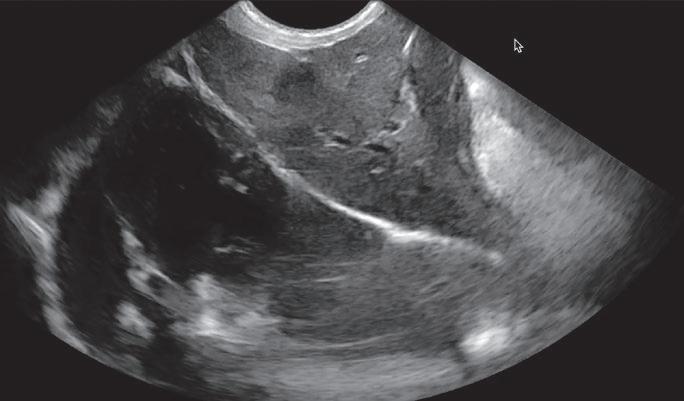

Para realizar la mayoría de los procedimientos quirúrgicos, es imprescindible disponer de un equipo de fluoroscopia, que permite la adquisición rápida de

La radiología intervencionista se realiza mediante un abordaje guiado por distintas técnicas de imagen como, por ejemplo, la ecografía, la fluoroscopia o la tomografía computarizada, para alcanzar la zona a diagnosticar o tratar.

La radiología intervencionista, también conocida como radiología vascular e intervencionista, es una especialidad que se encarga del diagnóstico y tratamiento de una gran cantidad de enfermedades de una manera mínimamente invasiva. Se realiza mediante un abordaje guiado por distintas técnicas de imagen como, por ejemplo, la ecografía, la fluoroscopia o la tomografía computarizada, para alcanzar la zona a diagnosticar o tratar.

La radiología vascular e intervencionista ofrece una alternativa segura y eficaz a la cirugía en muchas enfermedades. Entre sus ventajas para el paciente destaca una menor agresión a nivel tisular, una rápida recuperación, procedimientos sin dolor, rápidos y seguros, un menor coste respecto a otras muchas cirugías con mis-

imágenes basadas en rayos X y posteriormente las convierte en una señal de vídeo en tiempo real. Estas imágenes pueden manipularse ofreciendo funciones como la angiografía de sustracción digital, mapeo vascular y ampliación. Respecto a una radiografía, la exposición de rayos X necesaria para realizar una fluoroscopia es baja, pero debido a la duración de las series de imágenes que habitualmente se toman, el nivel de exposición en los pacientes suele ser elevado. Por lo tanto, es importante controlar el tiempo de exposición y llevar un registro de este. El fluoroscopio debe estar situado en una sala adecuada para su uso seguro, y todo el personal que entre en la sala de fluoroscopia debe protegerse de la radiación utilizando un delantal plomado, protectores de tiroides y gafas plomadas.